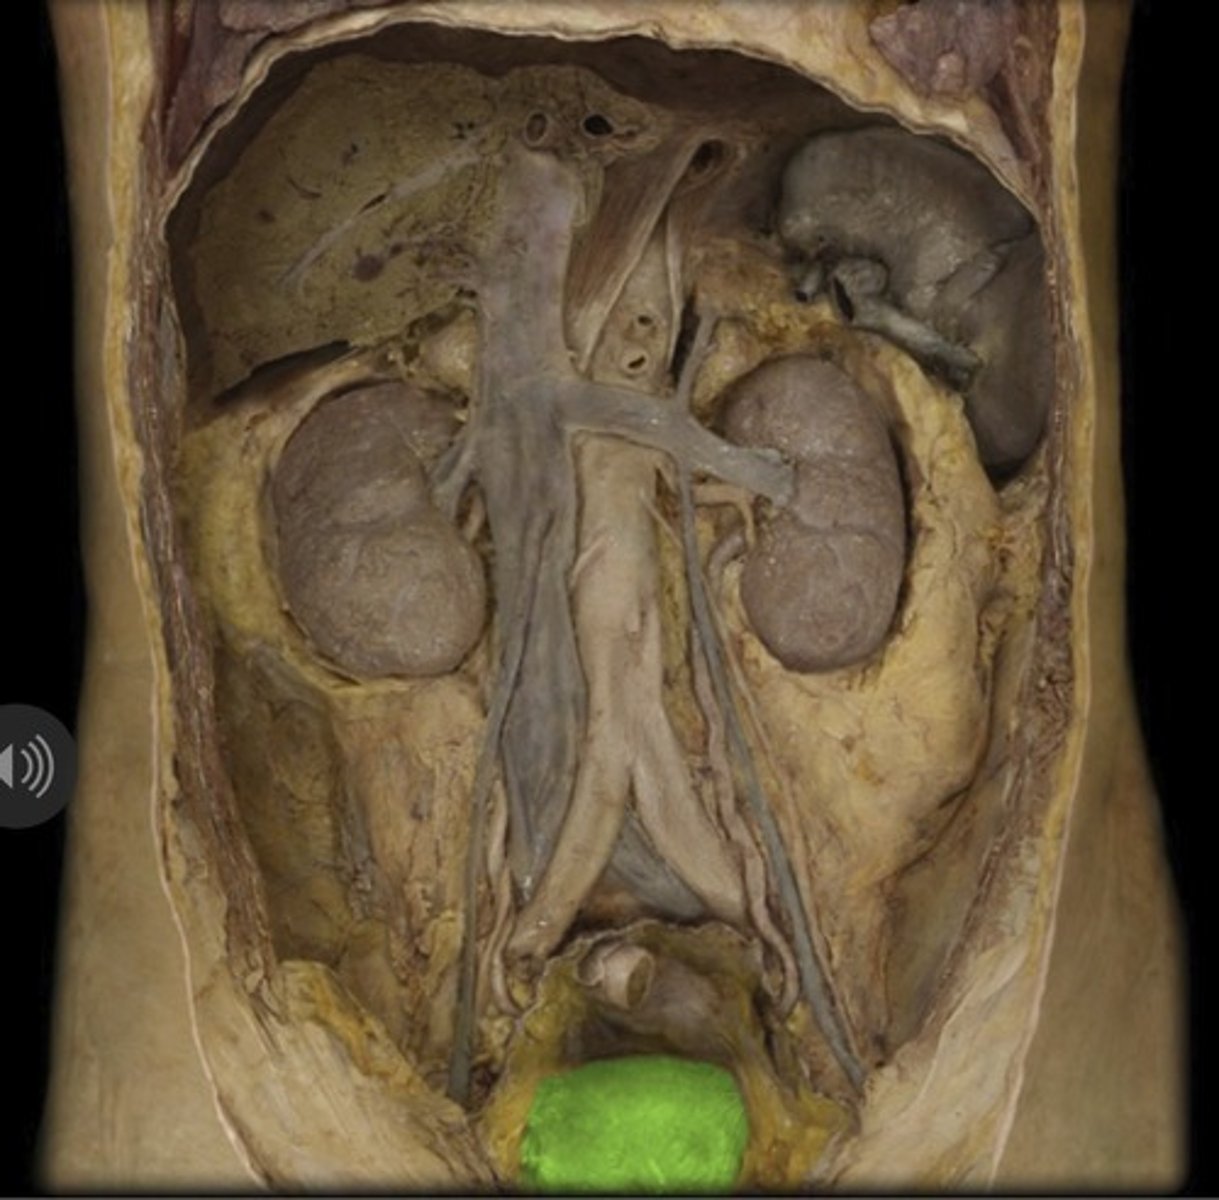

Urinary Bladder

Urinary Bladder